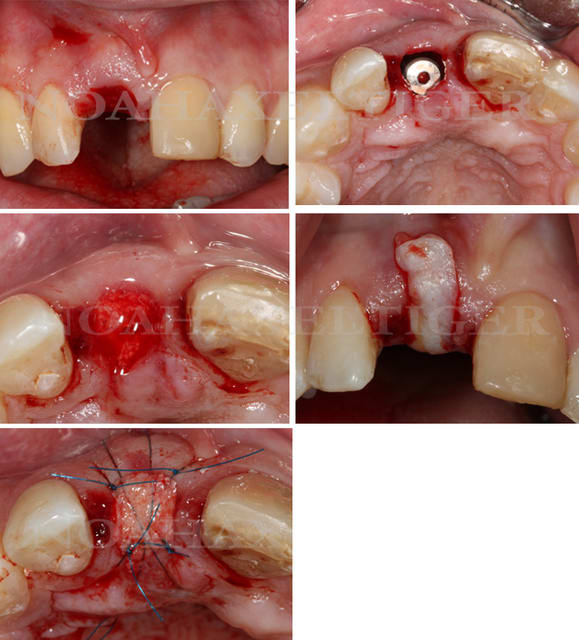

Ce cas est limite et aurait pu être traité en deux temps mais bon, j'ai opté pour y aller franco...

La seamine prochaine je vous montrerai la finition céramique.

Bon la suite des photos mais il faut commencer par la dernière, l'ordre de passage lors de l'envoi s'est apparemment inversé...

Zut, l'ordre des photos n'est pas celui que j'avais prévu, vous voudrez bien remettre dams l'ordre en lisant les titres. Le logiciel d'eugénol mélange tout à sa guise...

Tout à fait d'accord growler et c'est d'ailleurs ce que l'on peut voir sur le cas suivant. Fracture radiculaire, aucune infection periradicualire. Extraction et implantation immediate. Espace existant entre l'implant et l'alvéole est comblé par du BioOss. Un logement sous gingival est formé en vestibulaire et palatin de facon à pouvoir recouvrir le tout par BioGide et un conjonctif enfoui.

L'implant est de 15mm mais l'alvéole était large et 50% environ de la surface implantaire n'était en contact qu'avec du BioOss. J'ai pour cela préféré enfouir.